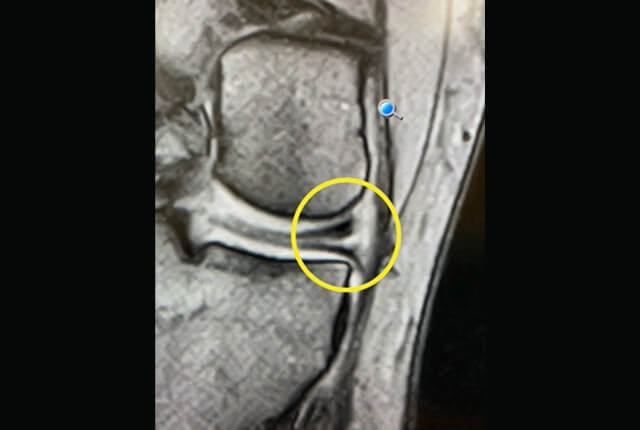

• MRIでACL損傷や半月板損傷を確定診断

診断1